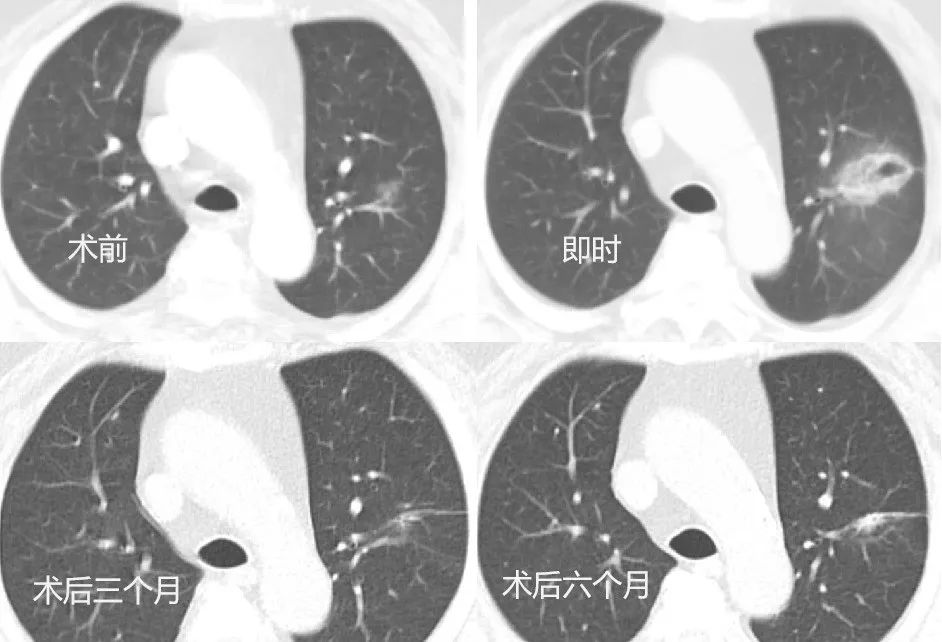

针对肺部多发结节治疗难题,天津医科大学总医院肺部肿瘤外科创新推出 “胸腔镜微创 + 冷热复合式消融” 的 “杂交手术” 模式。该技术避免传统手术对肺功能的损伤,让无法单一术式根治的患者获得更彻底治疗,目前占科室消融治疗总量 10%,实现肺功能保护与肿瘤控制率双提升。在此基础上,科室将冷热复合式消融技术应用于局部晚期肺部肿瘤的姑息治疗,与靶向、免疫、放疗等手段结合,形成 “局部 - 全身” 全程化管理模式,有效缓解患者症状、控制病情、延长生存期。

经过一年实践,冷热复合式消融技术已成为科室肺部肿瘤治疗的核心技术,塑造了学科特色优势与品牌竞争力。